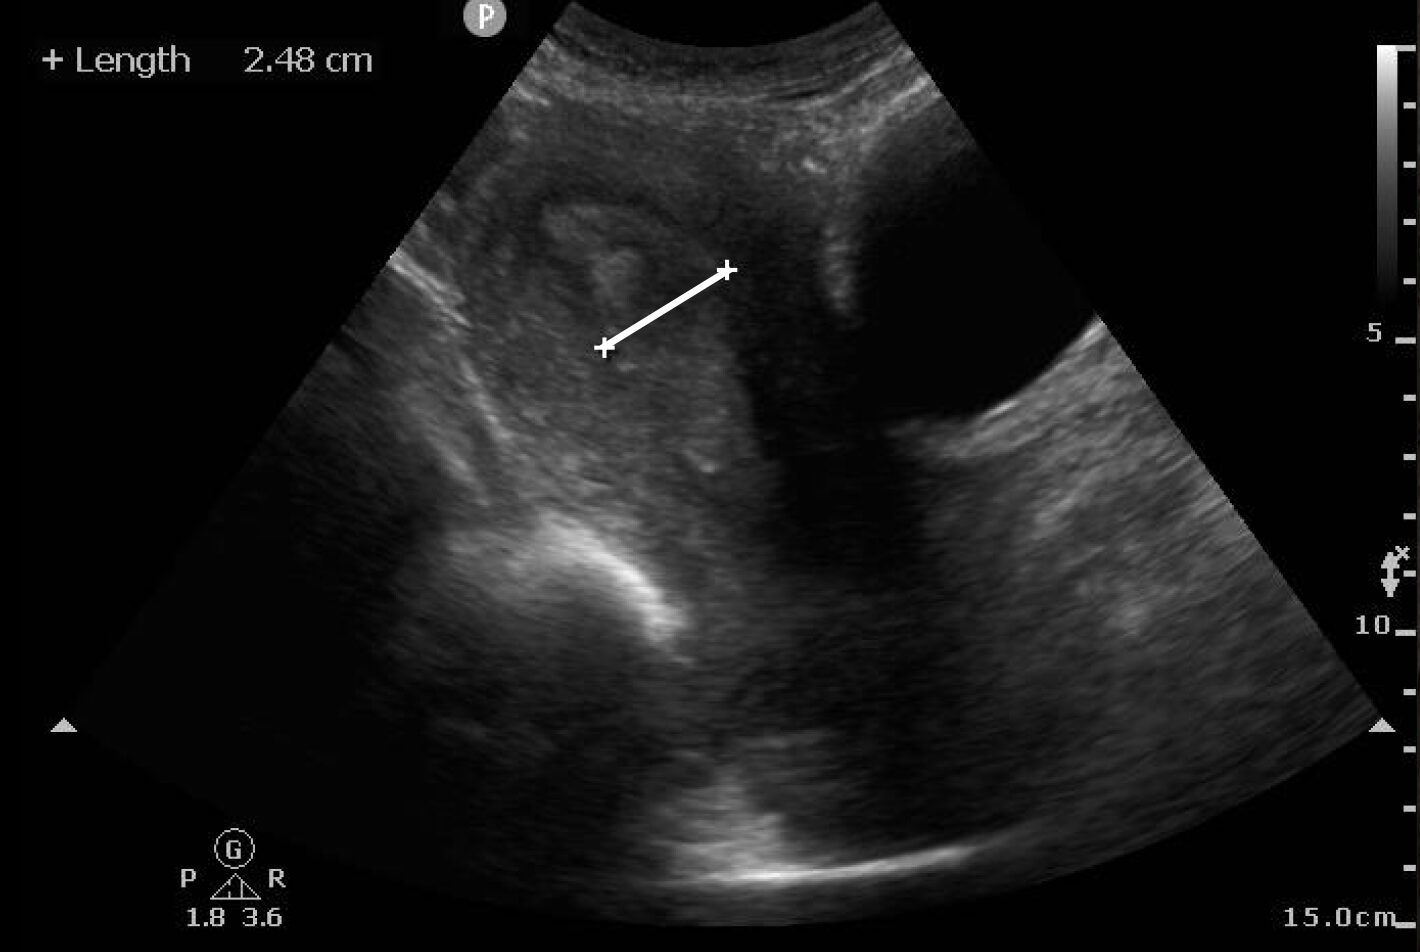

POCUS for identification of RPOC starts with visualization of the uterus and endometrial stripe, using the bladder and vaginal stripe as landmarks (Image 1) (Video 1). To perform the scan, place the probe in the sagittal plane superior to the pubic brim. The normal uterus appears homogeneous and isoechoic or hyperechoic. The endometrium is located centrally within the uterus and appears more hyperechoic. Fanning the probe can help identify the endometrium, which then can be measured within the uterus in the sagittal plane, at the thickest area of echogenicity, without the inclusion of fluid or myometrium (Image 2) if there is concern for RPOC.

Image 1: Sagittal view of the uterus in early pregnancy

Image 2: Measured endometrium that appears thickened and heterogeneous